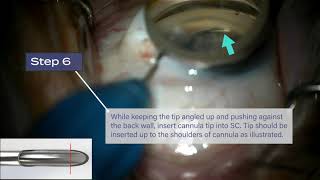

iTrack™ Procedural Steps: Hub Placement, Left Handed Approach video

iTrack™ Procedural Steps: Hub Placement, Left-Handed Approach

iTrack™ Procedural Steps: Hub Placement, Left-Handed Approach